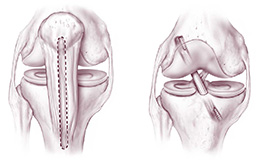

Il legamento crociato anteriore non può essere suturato; è necessario ricostruirlo utilizzando innesti tendinei che fungono da impalcatura su cui si formerà un neo-legamento. Gli innesti autologhi (prelevati dal paziente stesso) più frequentemente utilizzati sono il tendine rotuleo e i tendini flessori del ginocchio (gracile e semitendinoso). Si possono eventualmente utilizzare anche innesti omologhi (da cadavere).

La tecnica chirurgica prevede la preparazione di 2 tunnel ossei (tibiale e femorale) entro cui viene fatto passare il trapianto debitamente preparato che verrà poi fissato con viti o pin (metallici o di materiale riassorbibile).